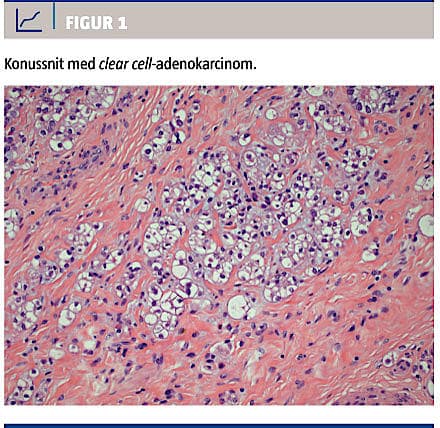

Med henblik på afklaring af diagnosen foretoges abrasio og konisation i generel anæstesi. Undersøgelsen af konus viste et 3 × 3 × 5 mm fokus med samme tumorvæv, som blev påvist i polyppen (Figur 1).

Der var ingen karinvasion, og resektionsrandene var frie. Abrasio var normal. Også konuspræparatet blev sendt til second opinioni Baltimore. Den endelige konklusion blev, at der var tale om et clear cell-adenokarcinom med primært udgangspunkt i cervix. Hvis karcinomforandringerne i polyp og konus var sammenhængende, var der tale om stadium IB1.